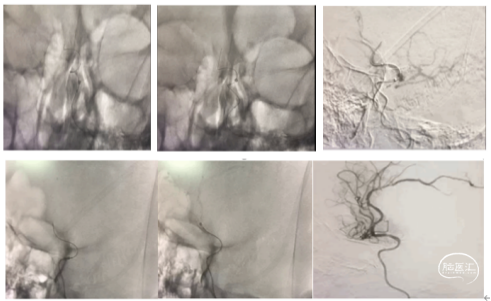

治疗方案:

大脑前动脉血管较细、路径迂曲,一般抽吸导管到位比较困难,又恐4mm及以上直径的取栓支架用于大脑前动脉对血管损伤较大,遂使用3*20mm小支架联合5F 125中间导管,SWIM取栓。

手术所用耗材:取栓支架 3*20mm、远端通路导管 5F 125cm 、0.014inch 300cm微导丝、2.4F微导管、6F长鞘、0.035in泥鳅导丝、5F造影导管。

手术过程:

1、微导丝越过闭塞处到达A3段。下图1

2、5F 125中间导管辅助高到位下图2。

3、手推造影明确血栓位置下图3。

4、微导管到达A4段下图4。

5、3*20取栓支架到位回撤微导管,多点显影标记,清晰可见支架打开良好下图5。

造影显示血管再通。

术后管理

术后替罗非班6ml/h 持续泵注24小时桥接双抗治疗,术后使用依达拉奉右崁醇 30mg 2次/日,监测血压维持在收缩压140mmHg左右。